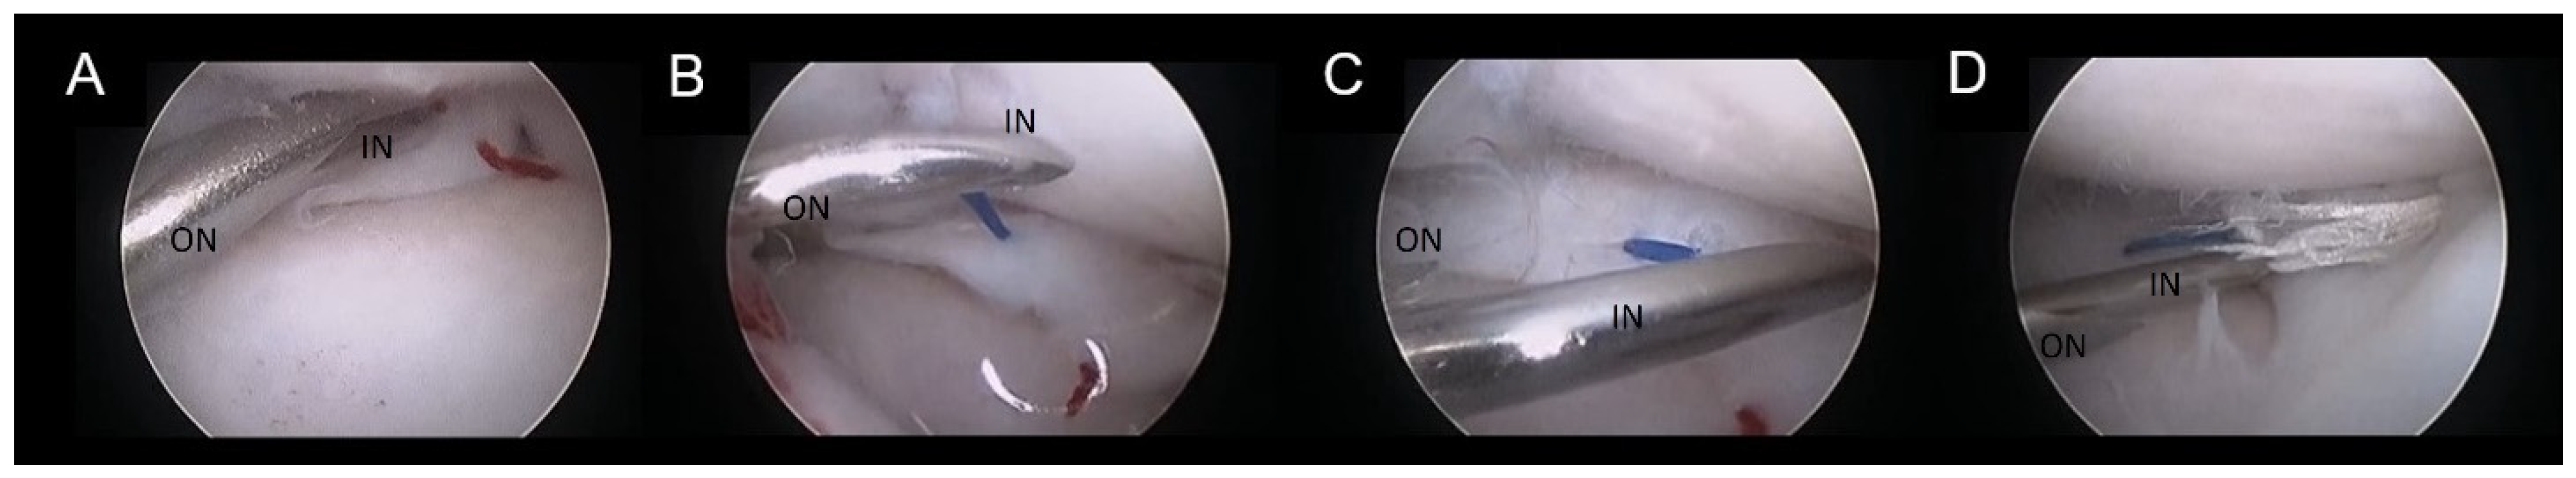

Figure 2. Double needle suture technique. Intraoperative picture of different steps of meniscal suture repair using the double needle technique in a right stifle joint: (A) The double needle construct is placed in position, and the spinal needle (IN) is passed through the meniscus, while the 16G needle (ON) is holding the meniscus in position. (B) The spinal needle is retrieved within the joint holding the suture. (C) The spinal needle drives the strand of suture in a different area of the meniscus over the lesion. (D) The suture loop is passed through the meniscus more abaxially and outside the joint to the caudo-medial area of the stifle where the needle is retrieved.

2.3. Meniscal Sutures

Suture application for meniscal tears was performed in meniscal lesions located in the abaxial third of the meniscus (red-red zone, as illustrated in Figure 1) when an adequate amount of healthy tissue was present to ensure a robust suture hold. The suturing technique employed was the double needle method, an evolution of the single-needle technique already described [8]. A 22-G spinal needle (inner needle, IN) was passed through the lumen of a 16-G standard needle (outer needle, ON) (Figure 2). The assembly was introduced through the cranio-lateral portal and navigated in a caudo-medial direction until contact with the meniscal surface was reached. Subsequently, the spinal needle was advanced through the meniscus plan to the lesion and across the lesion site (Figure 2A). It was then pushed through the joint capsule, emerging in the caudo-medial aspect of the stifle joint, where the needle tip was palpated and exposed by a stab incision. Soft tissue dissection was meticulously performed to reveal the needle tip. The needle trocar was removed. The suture material was then inserted into the inner needle’s tip and advanced until caught at the needle cone, secured by manual grasp. Retracting the inner needle tip back into the joint rendered the suture strand visible within the joint (Figure 2B). While the outer needle maintained meniscal stability and kept a working distance between the meniscus and the scope, a suture loop was created. The inner needle’s bevel was rotated. The spinal needle was once more propelled through the meniscus abaxial to the initial insertion (Figure 2C,D), pushing the suture through the meniscus. Vigilance was exercised to prevent suture damage by the needle’s tip. In case of suture damage, the procedure was repeated. Upon the needle tip’s re-emergence at the joint capsule, the suture loop was retrieved from the needle tip, and the extremity was pulled out, leaving the two extremities of the suture exiting from the wound. Following needle removal, the two suture ends were carefully tightened without tension by a square knot and 4-5 secure knots, ensuring the meniscal segments were closely apposed without gap formation or bulging. Sutures were applied in cross, horizontal or vertical configuration (Figure 3). The process was repeated as many times as needed to meet clinical requirements (Figure 2 and Figure 3) and achieve a secure hold by the sutures. The choice of suture type and material was tailored to each patient, with 2-4 crossed and horizontal or vertical mattress sutures executed using polypropylene (Prolene® USP 3-0, Ethicon) and/ or polydioxanone (PDS II®, USP 3-0, Ethicon) (Table 1). Any complication encountered was recorded.

The breeds included were Cane Corso (n=2), Labrador (n=1), Dobermann (n=1), German Shorthair (n=1), Boxer (n=1), Maremmano-abruzzese (n=1) and mixed breed (n=1) with an average age of 5.28 years (range, from 1.8 to 11.5 years). Two of the dogs underwent treatment for both limbs at different times. The mean body weight was 36 kg ± 7.1 kg (range 24 to 48 kg). Three male and five female, six left and four right stifles were included in the study. Preoperative blood tests showed no abnormalities. Presurgical radiographic evaluation revealed joint effusion of the stifle in all dogs. The arthroscopic assessment was performed in all dogs without distraction for preliminary evaluation. When the meniscal lesion was detected or some abnormality required further evaluation, the distractor was applied to the limb. Sufficient distraction allowed for the evaluation of both menisci in all cases with slight difficulties in visualization in two cases (Table 1). Findings confirmed a complete cranial cruciate ligament rupture in all dogs, and meniscal lesions were identified in the abaxial third of the caudal horn of the medial meniscus (Table 1, Figure 2). Utilizing the double-needle technique, meniscal suturing was successfully performed in all dogs with surgical times ranging from 42 to 83 minutes (average 64 minutes ± 22 minutes). The suturing was done by two stitches in four cases, three stitches in four cases, and four stitches in one case. Of the total number of twenty-seven stitches, twenty-one were vertical, two were horizontal and four were crossed. The suture materials used were nonabsorbable polypropylene (sixteen stitches) and polydioxanone (eleven stitches) (Table 1).